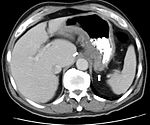

CT and MRI scans are useful for evaluating the small bowel with enteroclysis protocols.They are additionally useful for looking for intra-abdominal complications of Crohn's disease such as abscesses, small bowel obstruction, or fistulae. Magnetic resonance imaging (MRI) are another option for imaging the small bowel as well as looking for complications, though it is more expensive and less readily available